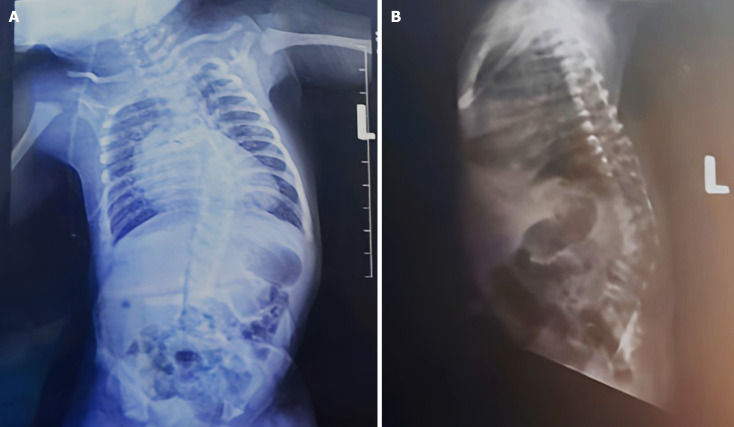

Case summary: We present a 36-week preterm neonate with CS associated with TA type 1, presenting with respiratory distress, cyanosis, and altered spinal curvature. This case demonstrates the complexity of managing neonates with multiple congenital defects. Here, the patient was managed with oxygen supplementation, heart failure medication, nasogastric feeding, and multidisciplinary care to optimize her for surgical corrections. A coordinated, interdisciplinary approach was employed to optimize outcomes, particularly in a resource-limited setting. Immediate respiratory and cardiovascular stabilization and long-term orthopedic and cardiac interventions were central to improving the patient's quality of life and survival.